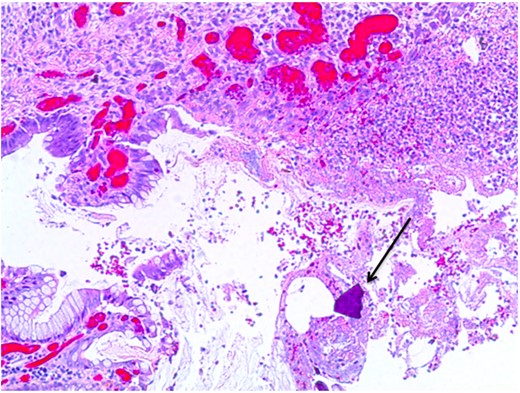

At pathological examination, the mucosa was diffusely hemorrhagic with extensive multifocal ulcerations. Crystalloid particles consistent with Kayexalate were identified throughout the bowel wall (Figs 1 and 2). There was no evidence of neoplasia or viral inclusions and cytomegalovirus immunostains were negative. Thus, a diagnosis of kayexalate-induced colon ischemia and necrosis was made.

Colonic ulceration with necrosis and kayexalate crystal identified.

The presence of kayexalate crystals on pathology specimens distinguishes kayexalate-induced necrosis from ischemic necrosis. Otherwise, these entities have a similar presentation. Identification of rhomboid or triangular, basophilic crystals with a mosaic pattern on hematoxylin and eosin (H & E) stain is pathognomonic for the presence of kayexalate (Figs 1 and 2). These crystals are identified adherent to the mucosa or imbedded within inflammatory milieu and ulceration [10].